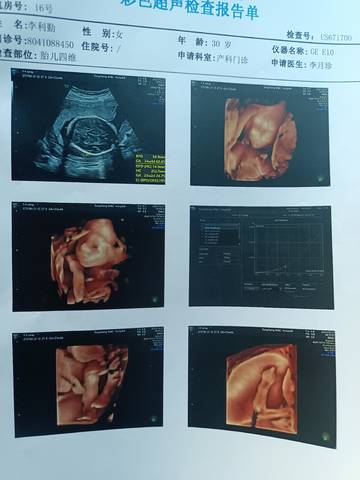

四维出来了,谁能看出来是男孩还是女孩呀?

journal_insert_pic_1687250905journal_insert_pic_1687252039

通过这些是看不出来的,而且也不准确,在怀孕期间,我觉得只要宝宝发育好的话,还是不要想太多了,男孩女孩都一样的。

你好亲爱的,通过这个来判断男孩女孩是不太准确的哈,我们要给他同等的关爱和呵护,也祝你可以如愿以偿,心想事成。

看不出来,这个单上的数据是很难直接判断男孩还是女孩的哦,其实只要孩子健健康康就好,生下来才最准

#妈妈问答大赛#发育健康的话就可以了,对于宝宝的性别的话是没有办法准确的判断出来的啦

你好,通过这个看不出来的,不管是男宝宝还是女宝宝,只要平安,健康就好。